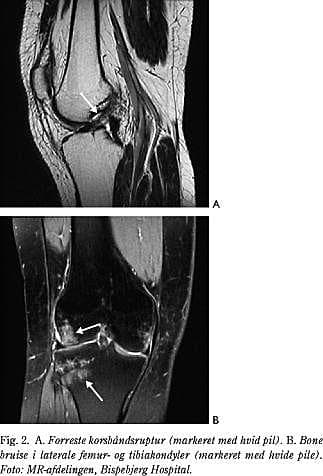

• afrivning af det forreste korsbånd med et knoglestykke fra eminentia tibiae (Fig. 3),

Derfor bør der altid tages røntgen ved mistanke om akut forreste korsbåndsskade. Ved klinisk mistanke om samtidig ruptur af det bageste korsbånd eller det posterolaterale hjørne kan subakut MR-scanning være indiceret som led i planlægningen af operativ behandling i den akutte fase.

Hos ca. 5% (og hyppigere hos børn) med akut forreste korsbåndsinstabilitet er korsbåndet ikke revet over, men eminentia tibia, som korsbåndet hæfter på, er afrevet (Fig. 3). Ved akut osteosyntese af eminentia kan korsbåndsstabiliteten reetableres i langt de fleste tilfælde.